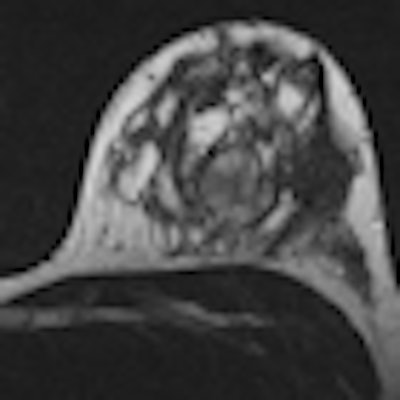

Utilizing MR for dense breasts saves biopsies, money

March 10, 2013 -- VIENNA - Adding dense breasts as a new standard indication for MR mammography in cases with unclear findings could ward off approximately 88% of biopsies and end up saving insurance companies money, according to research presented on Sunday morning at ECR 2013.